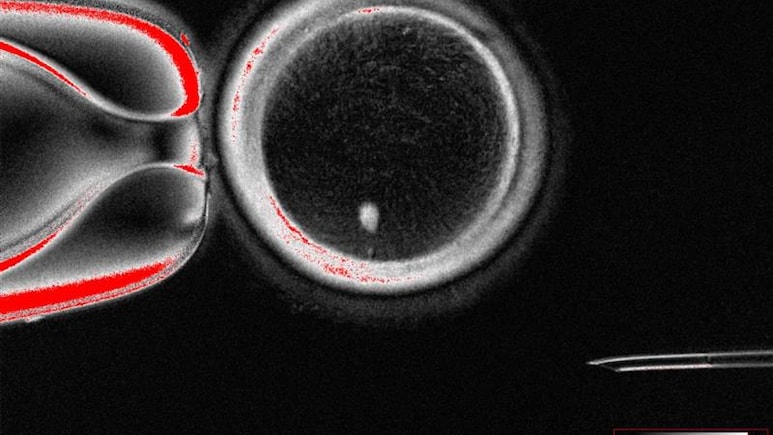

The scientists first removed the nucleus from normal skin cells and transferred them into a donor egg which had its nucleus removed. This technique, called somatic cell nuclear transfer, was used to clone Dolly the sheep in 1996.

The scientists managed to remove these extra chromosomes using a process they are calling "mitomeiosis", which mimics how cells normally divide.

They created 82 developing eggs called oocytes, which were then fertilised by sperm via in vitro fertilisation (IVF).

After six days, less than nine percent of the embryos developed to the point that they could hypothetically be transferred to the uterus for a standard IVF process.